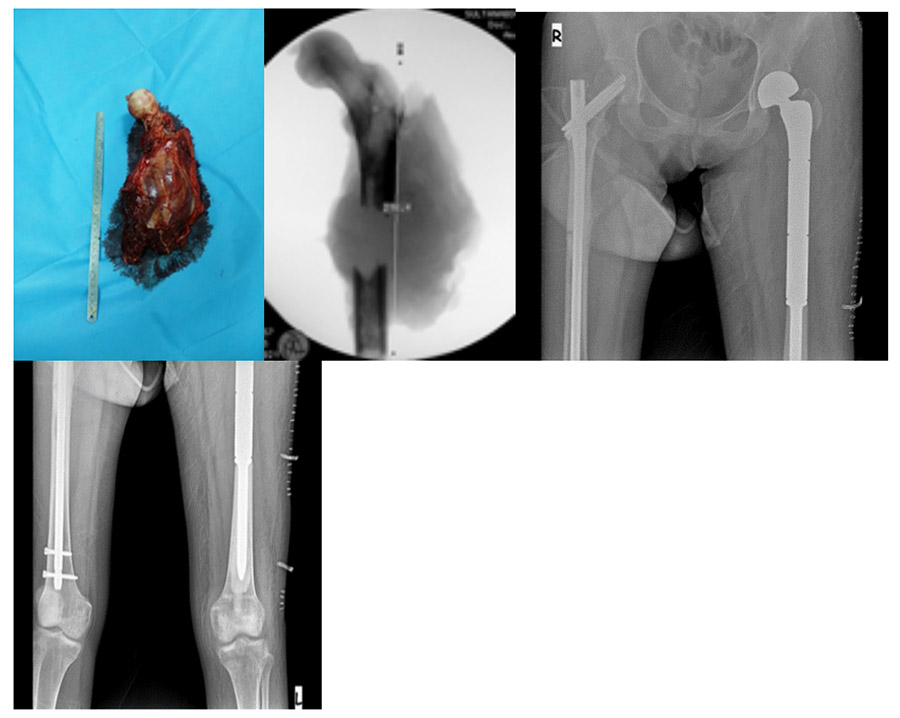

During and after surgery: The clinical and fluoroscopy images of the removed tumor and fractured upper femur, as well as the cemented tumor prosthesis implanted in place of the removed upper femur, are shown.